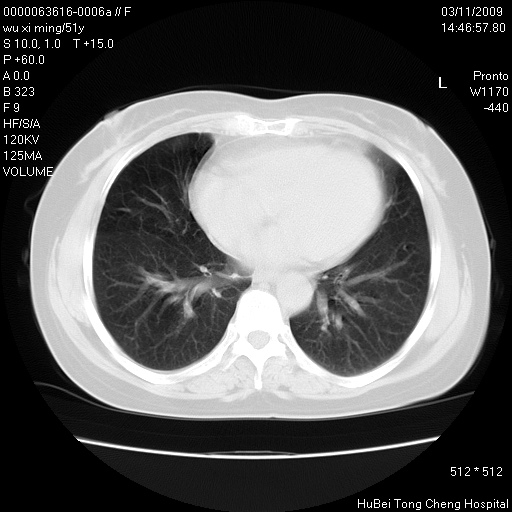

患者 女,51岁。因“胆囊炎,胆囊结石”,行常规术前胸部x线检查发现:右上肺结节病灶,建议行进一步检查。患者无咳嗽、咳痰及咯血等呼吸道症状,近期出现背部疼痛不适。

胸部ct轴位平扫(层厚10mm,螺距1.5,重建间隔10mm;部分层面:层厚3mm,螺距1.0,重建间隔3mm),图像如下:

考虑右肺癌肺内转移!

右肺周围型肺癌伴肺内转移信胸椎转移

1、周围型肺癌。(毛刺正、血管束集征,分叶。)